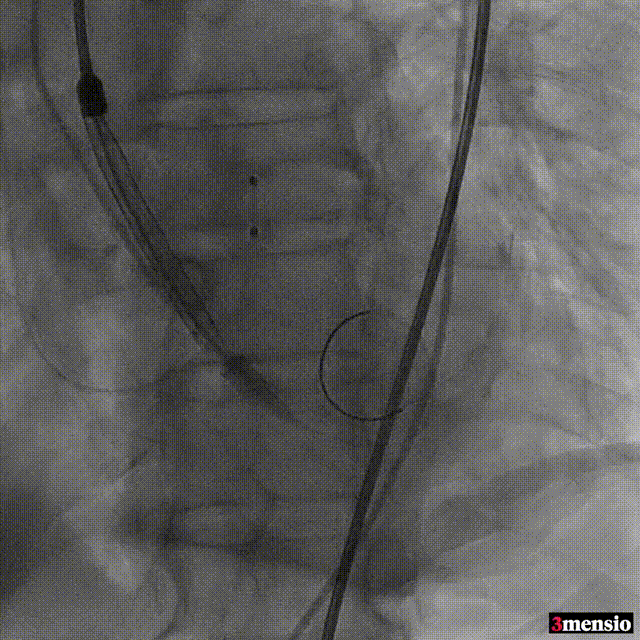

唐熠达教授团队对病例进行多学科综合分析评估决定行一站式PCI+TAVI手术,结合患者91岁高龄,主动脉根部结构及双侧劲动脉粥样硬化斑块形成,脑动脉硬化情况采用20mm球囊预扩,拟植入VenusA-Valve L26瓣膜。

手术过程

根部造影

跨瓣

20mm球囊预扩

标准位释放定位

23mm球囊后扩

术后造影

瓣膜定位精准,标准位释放,轻微瓣周漏,术后效果良好,手术取得圆满成功。